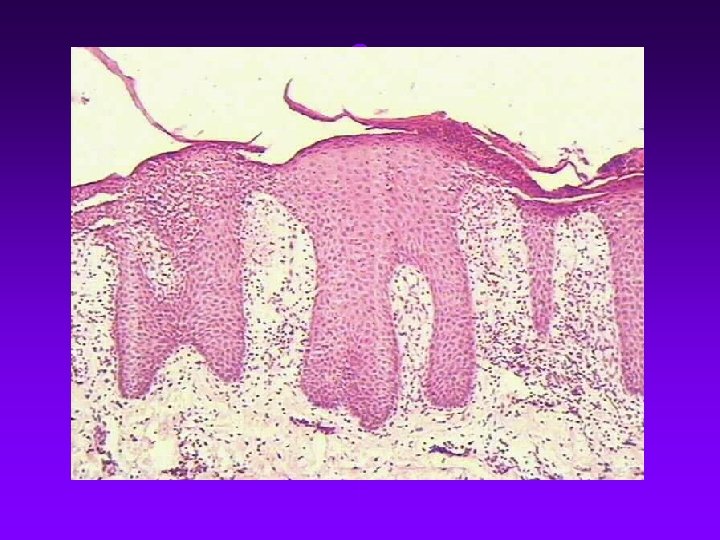

Definition Psoriasis is a recurrent, chronic, inflammatory disease of the skin characterized by red papules or plaques covered by silvery white and multilayer scales.

p. vulgaris: red papule silvery white scales Film phenomenon Auspitz’s sign